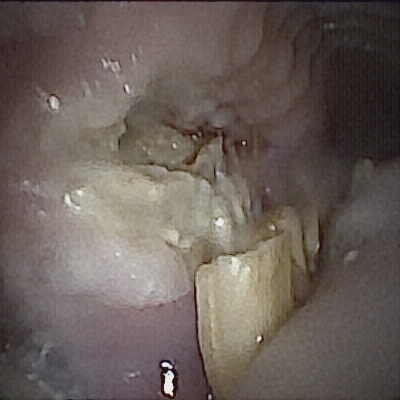

Leider hat der Termin im Tierzahnzentrum in München keine guten Nachrichten gebracht. Floreas rechte Wangeninnenseite war komplett aufgelöst und voller Eiter. Die Tierärztin geht davon aus, dass das von dem veränderten Knochen, den man am CT schon gesehen hatte, ausgeht. Beim letzten Termin war davon nichts zu sehen, eine so rasante Ausbreitung einer Infektion ist nie ein gutes Zeichen. Sie hat uns zur Euthanasie geraten und nachdem wir die Fotos gesehen hatten, haben wir uns ebenfalls dafür entschieden, um ihr weiteres Leid zu ersparen. Gerne hätten wir ihr noch ein langes und schönes Leben geschenkt, doch das Schicksal meinte es anders. Mit nur eineinhalb Jahren ist Floreas Leben zu Ende gegangen.